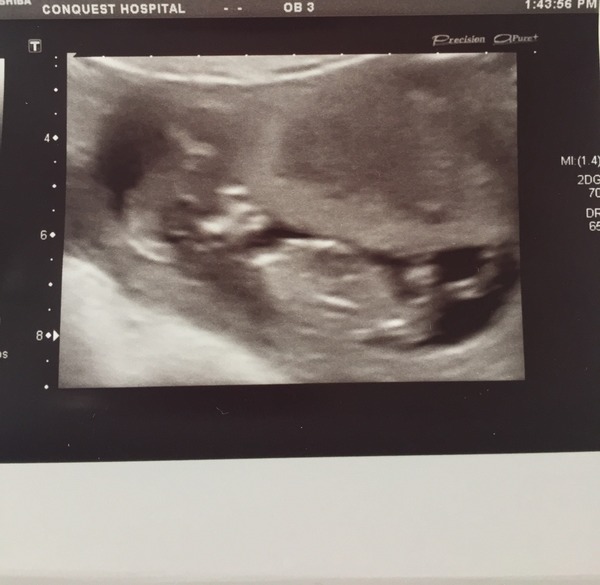

obsessedlex · 04/04/2016 20:54

Thanks everybody - we are thrilled!

Now are there any nub theory experts out there? (I don't think the pictures are good enough)

I searched high and low for an early scan in my area no luck so found a place in Cardiff which is quite far. Well I had an abnorminal scan. Measuring 6 weeks my own dates using opk ovulation dates are 6.1 weeks. We saw with strong heart beat. She could not even see the bleeding. She assumes it's old implatation blood.

She didn't even want yo use the transvaginal scan because the picture is soooo good. We are so happy. 12 weeks scan next.